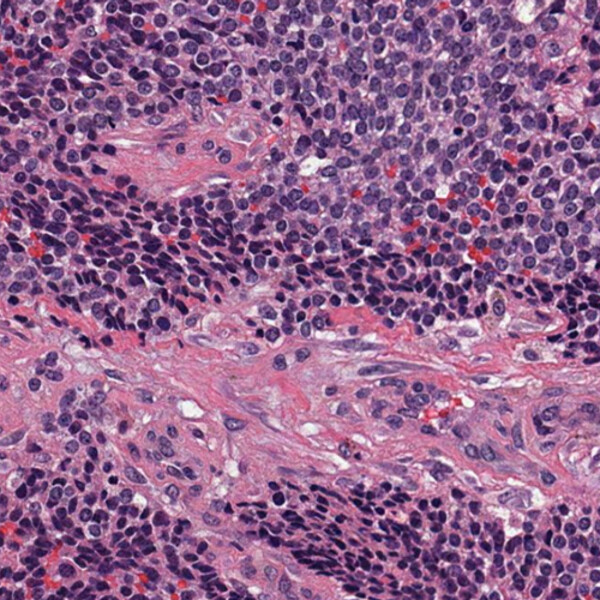

A 6-year-old girl is brought to the emergency room by her parents. She has developed a painless swelling on her left thigh that has gradually increased in size over the past two months. Initially, her parents thought it was a bruise or injury from playing, but the swelling became progressively larger and more firm. Recently, she has experienced some difficulty walking and now has a noticeable limp.